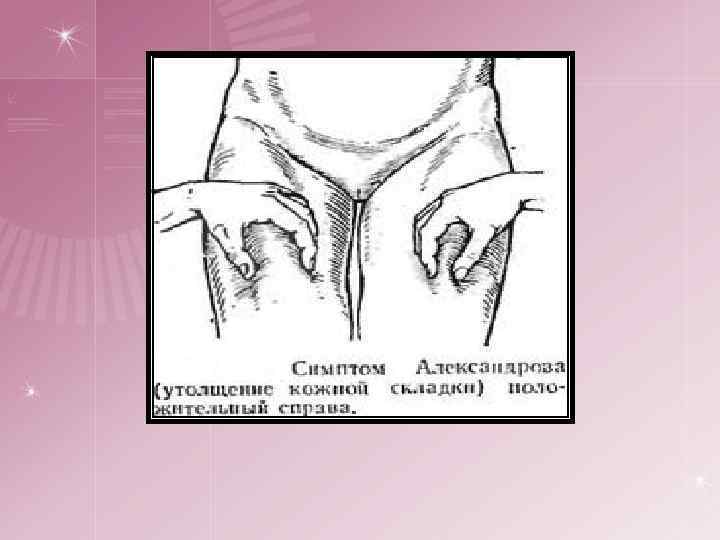

спондилическая артритическая Начальная стадия Общие - соответствует выходу туберкулезного процесса за пределы костного очага, поэтому сопровождается усилением туберкулезной интоксикации Местные: ¤ боли в позвоночнике, схожие с радикулитом, межреберной невралгией ¤ боли могут иррадиировать во внутренние органы ¤ ригидность мышц – ограничение движений в позвоночнике ¤ возникает симптом «вожжей» П. Г. Корнева переход туберкулезного процесса на сустав и развитие туберкулезного синовита. ¤ Постоянные боли, ригидность мышц, сглаженность контуров сустава, ограничение движений, хромота ¤ Слабовыраженные трофические расстройства: гипотония — ослабление тонуса мышц, атрофия мягких тканей, утолщение кожной складки на стороне поражения (симптом Александрова) При переходе туберкулезного процесса на сустав путем прорыва через суставной хрящ наблюдаются выраженные симптомы воспаления: высокая температура тела, быстро развившийся отек, параартикулярных мягких тканей, более редкое ограничение движений, блокада сустава.